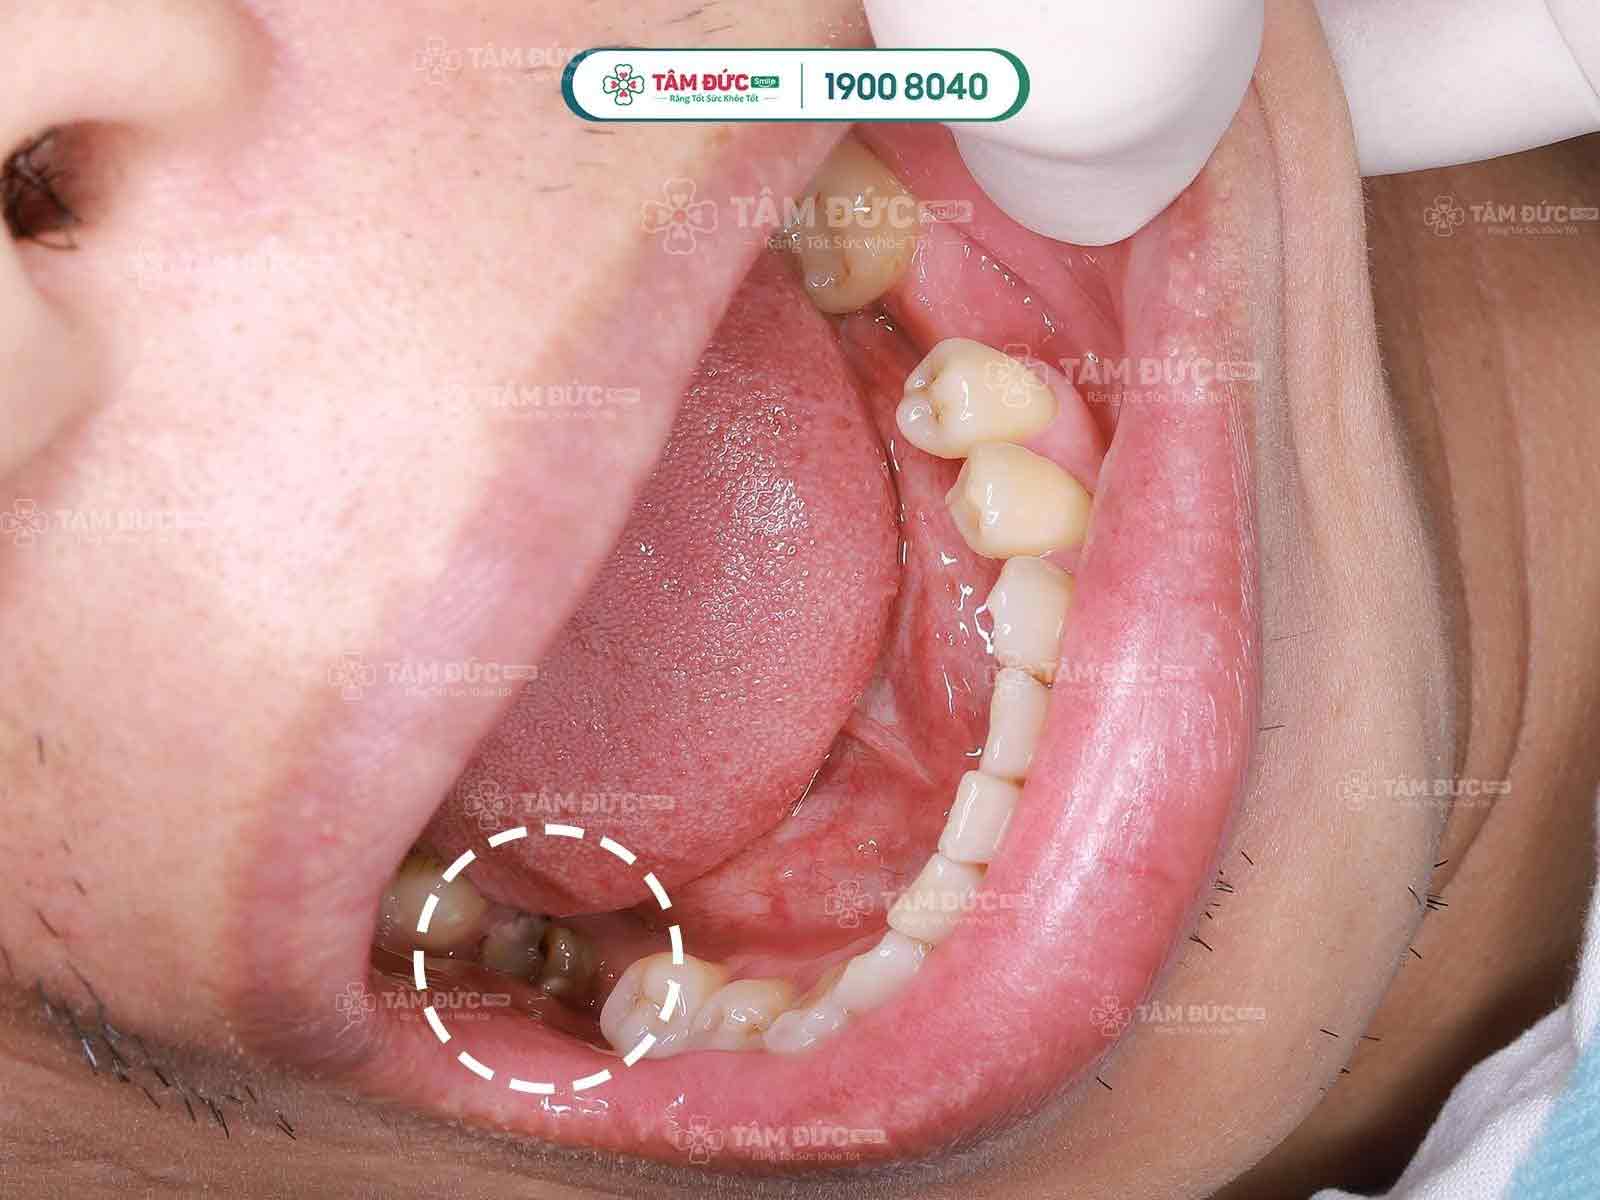

Tủy răng đóng một vai trò rất quan trọng đối với sức khỏe của răng, do đó các chuyên gia khuyến cáo khách hàng nên chữa tủy răng khi gặp phải bất kỳ một vấn đề nào đó liên quan đến tủy răng: Sâu răng, mẻ vỡ, đau buốt răng… tốt nhất bạn nên tìm đến tại các trung tâm nha khoa lớn để điều trị càng sớm càng tốt.

Tuy nhiên, khi tủy răng bị viêm thì toàn bộ răng của bạn sẽ bị giảm độ thẩm mỹ, ví dụ như răng ố vàng, sâu đen,... Với những khách hàng muốn có một sự hoàn mỹ cho hàm răng thì bọc răng sứ thẩm mỹ là một trong những lựa chọn tốt nhất. Với công nghệ bọc răng sứ tại nha khoa Tâm Đức Smile sẽ giúp bảo vệ răng gốc của bạn tối đa nhất sau khi điều trị viêm tủy răng, bên cạnh đó còn đảm bảo độ trắng sáng cho nụ cười của bạn lâu dài. Giá bọc răng sứ thế nào cũng phụ thuộc vào chất lượng sứ bạn lựa chọn (sứ kim loại và toàn sứ).